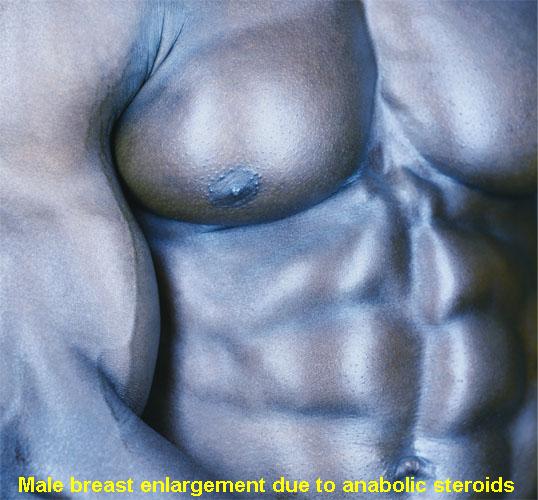

45_14Gynecomastia